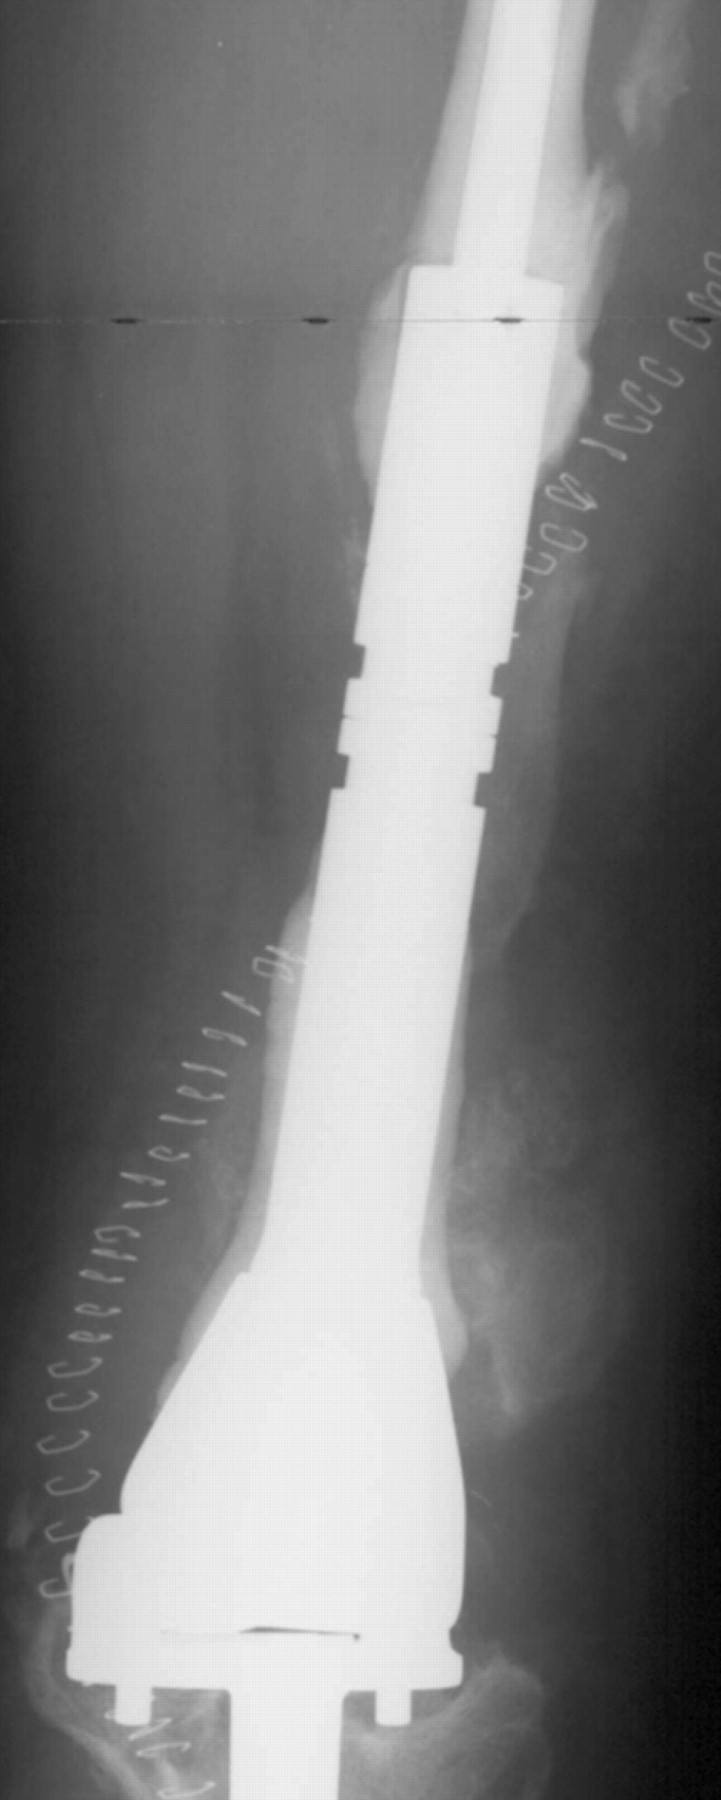

New STANMORE 22734 JTS (NonInvasive) Extendible Proximal Femoral

New STANMORE 22734 JTS (NonInvasive) Extendible Proximal Femoral Stanmore Jts The design eliminates the need for multiple lengthening. Stanmore implants (stanmore), specialists in the design and manufacture of patient specific implants for complex orthopaedic. The jts® extendible distal femoral implant is a modification to the jts®0 extendible implant. Onkos, which specializes in solutions for musculoskeletal oncology and other complex orthopedic conditions, said in a news release that. Intended use the. Stanmore Jts.